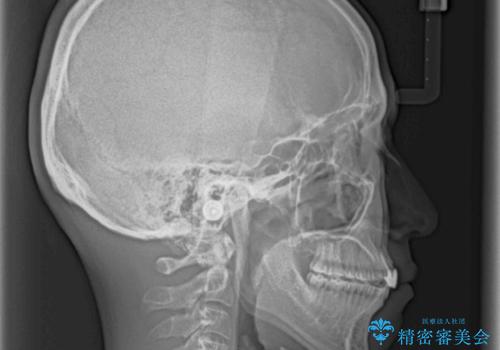

- 前歯の歯並びと不自然な色をした前歯のクラウンを気にして来院された患者様です。

上下前歯の歯列不正はインビザラインにより歯列を整え、その後に、前歯をオーダーメイドタイプのオールセラミッククラウンにて補綴治療することとしました。

初診時には、歯並びを整えることのみを検討されていましたが、歯列が整うにつれて不自然な色合いが気になるようになり、矯正治療を行ってから補綴治療をする計画を受け入れてくださいました。

口元の印象が明るく変わり、患者様には大変満足していただきました。